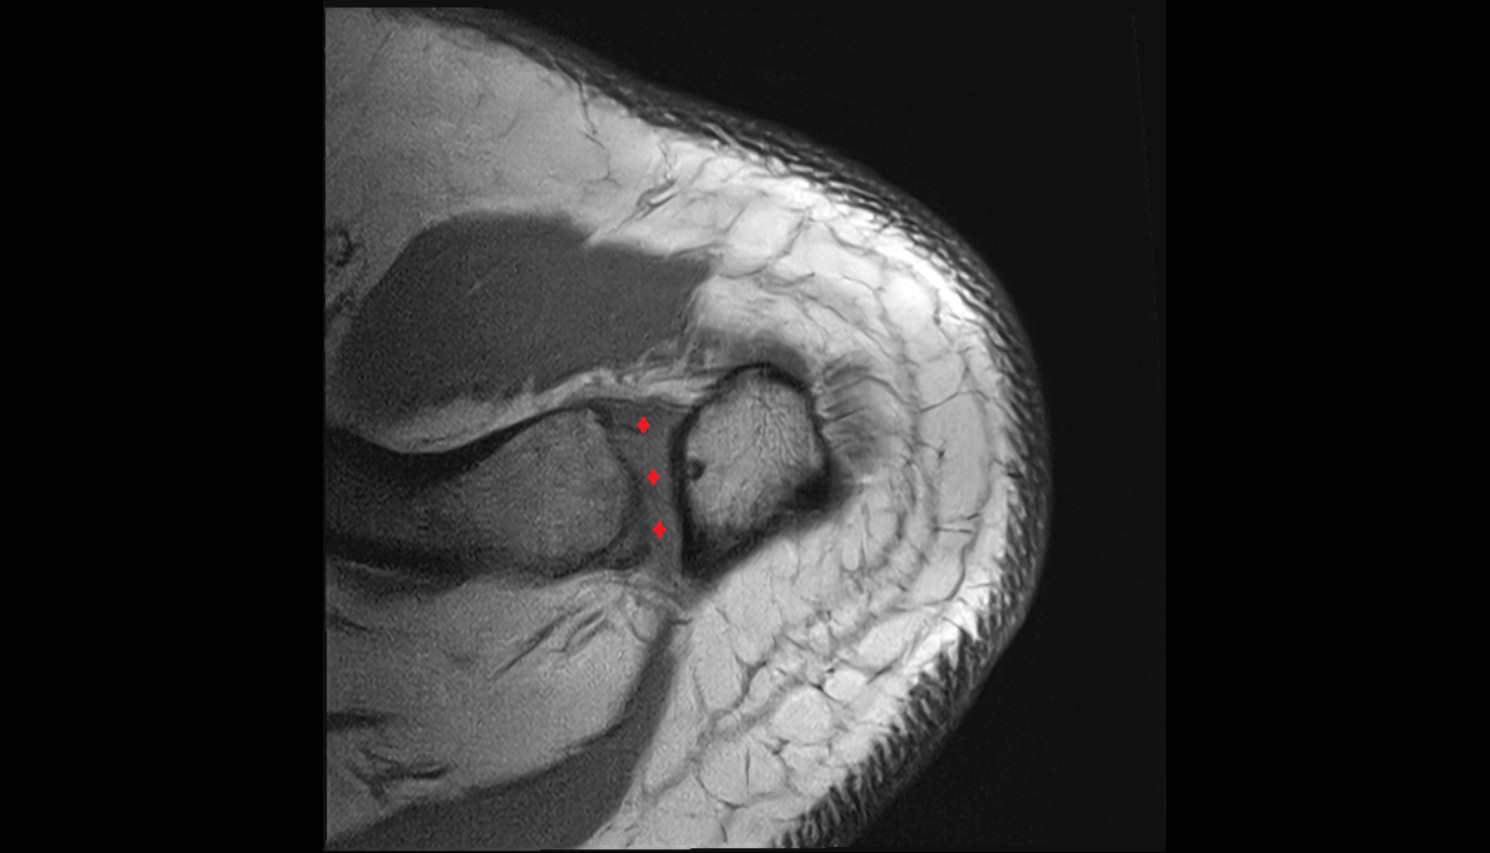

- Glenoid fossa

- Glenoid labrum

- Shoulder joint (glenohumeral joint)

- Articular cartilage of glenoid fossa